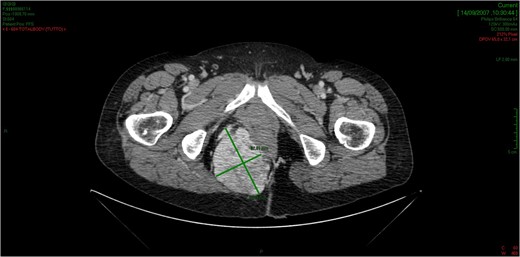

CT showed an hyperintense and inhomogeneous solid lesion taking up the right ischiorectal fossa (maximum diameter of about 10 cm), extended cranially until impressing the wall of the rectal ampulla, with no apparent infiltration (Figs 2 and 3). The lesion presented an intense contrast enhancement, sign of a rich vascularization (Fig. 4).

The lesion extends cranially until impressing the wall of the rectal ampulla, with no apparent infiltration.